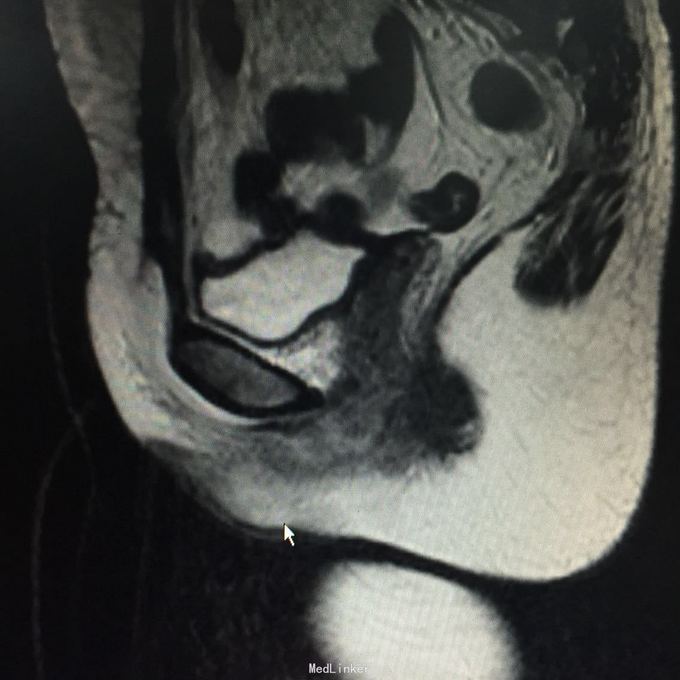

查体:会阴部位可及一大小约3*2cm质硬肿物,边界清,无压痛。阴道残端愈合可。辅助检查:HPV-DNA、LCT未见异常,阴道镜检查:会阴肿物,性质待查。彩超体表肿物:阴道口左侧低回声团,范围约42*20mm,肿块距体表1.8mm,内见丰富血流信号。盆腔MR:宫颈癌根治术后改变,阴道残端下份、阴道口占位,建议活检,双侧髂血管旁、腹股沟多发稍大淋巴结。会阴部位肿物。彩超:子宫切除术后,盆腔未见明显占位,肝胆胰脾双肾输尿管膀胱未见异常。